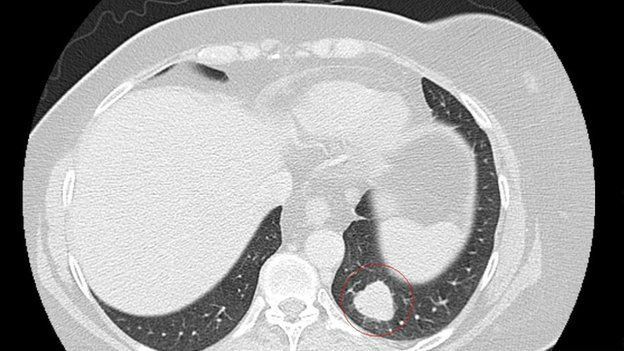

Томограма показує пухлину (обведену червоним) до лікування

Томограф показав, що після імунотерапії розміри пухлини сильно зменшилися